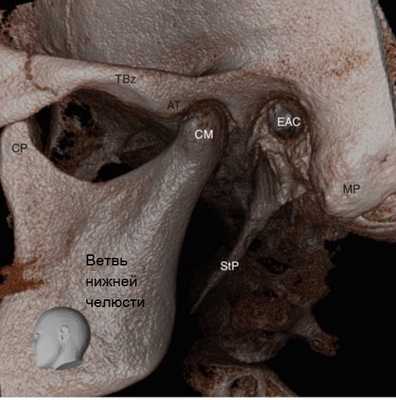

Височно-нижнечелюстной сустав (ВНЧС) — это синовиальный сустав, и он является единственный истинным суставом в челюстно-лицевой области. Он также известен как нижнечелюстной сустав, либо как черепно-нижнечелюстное сочленение. Височно-нижнечелюстной сустав является уникальным в связи с его вращательными (гинглимоидный сустав) и поступательными (артроидальный сустав) движениями во время функционирования нижней челюсти, включая открывание и закрывание рта, жевание и речь. Правый и левый суставы не могут двигаться независимо друг от друга, так как они соединяются через нижнюю челюсть, образуя двухмыщелковое сочленение (Alomar et al. 2007). Более того, зубы служат направлением и ограничивают определенные движения нижней челюсти. Как следует из названия, в образовании височно-нижнечелюстного сустава участвуют две кости, то есть височная кость и нижняя челюсть (Рисунок 1, 2, 3, и 4 ).

Рисунок 3 3D визуализация изображений конусно-лучевой компьютерной томографии левого височно-нижнечелюстного сустава у 62-летнего мужчины. АТ Суставной бугорок, СМ мыщелок нижней челюсти, СР венечный отросток, ЕАС наружный слуховой проход, МР сосцевидный отросток, StP шиловидный отросток, TBz скуловой отросток височной кости

Рисунок 4 Сагиттальный срез конусно-лучевой компьютерной томографии височно-нижнечелюстного сустава у 22-летней женщины. АТ Суставной бугорок, СМ мыщелок нижней челюсти, СР венечный отросток, ЕАС наружный слуховой проход, МF отверстие нижней челюсти

Суставная ямка височно-нижнечелюстного сустава образована нижнечелюстной ямкой, медиолатерально вытянутой полостью, расположенной в нижней части височной кости непосредственно перед наружным слуховым проходом (Рисунок 5 и 6). Суставная ямка спереди ограничена костным выступом - суставным бугорком. Головка височно-нижнечелюстного сустава — это верхняя часть мыщелкового отростка, который является задней частью ветви нижней челюсти и расположена напротив ее передней части - венечного отростка.